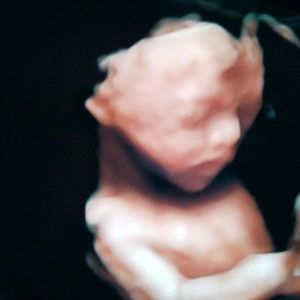

bun .. pasang Grito itu smpek umur brapa ya??

enggk pakek juga gpp Bunda.. atau sampai lepas tali pusar nya juga boleh Bund..

Sampai lepas tali pusarnya..trs pakai kaos